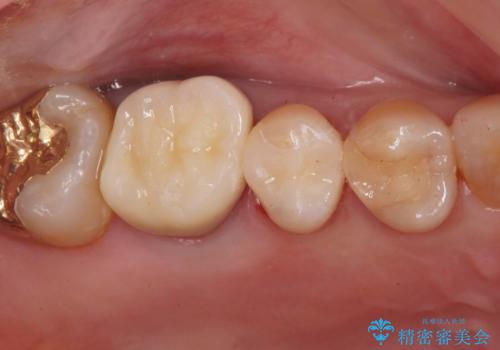

痛みの続く大きな虫歯の奥歯 オールセラミッククラウンでの補綴治療